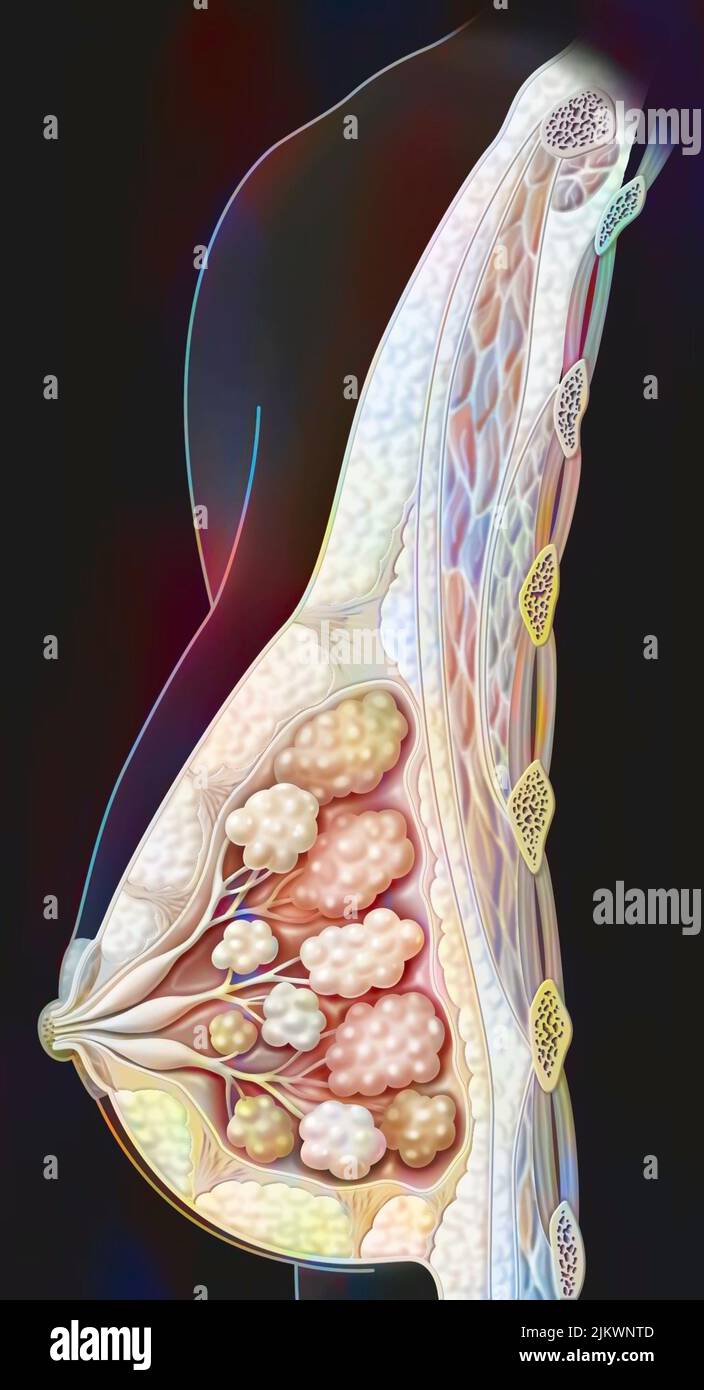

RF2JKWRM1–Vue antérieure des organes génitaux féminins avec vagin, utérus, trompes de Fallope, ovaires.